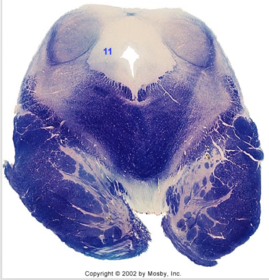

| Nucleus gracilis | |

| Accessory nucleus | |

| Medial longitudinal faciculus | |

| Pyramidal decussation | |

| Medullary pyramids | |

| Anterior spinocerebellar tract | |

| ALS | |

| Posterior spinocerebellar tract | |

| Spinal tract of V | |

| Spinal nucleus of V | |

| Nucleus cuneatus | |

| Fasciculus cuneatus | |

| Fasciculus gracilis | |

| Central canal | |